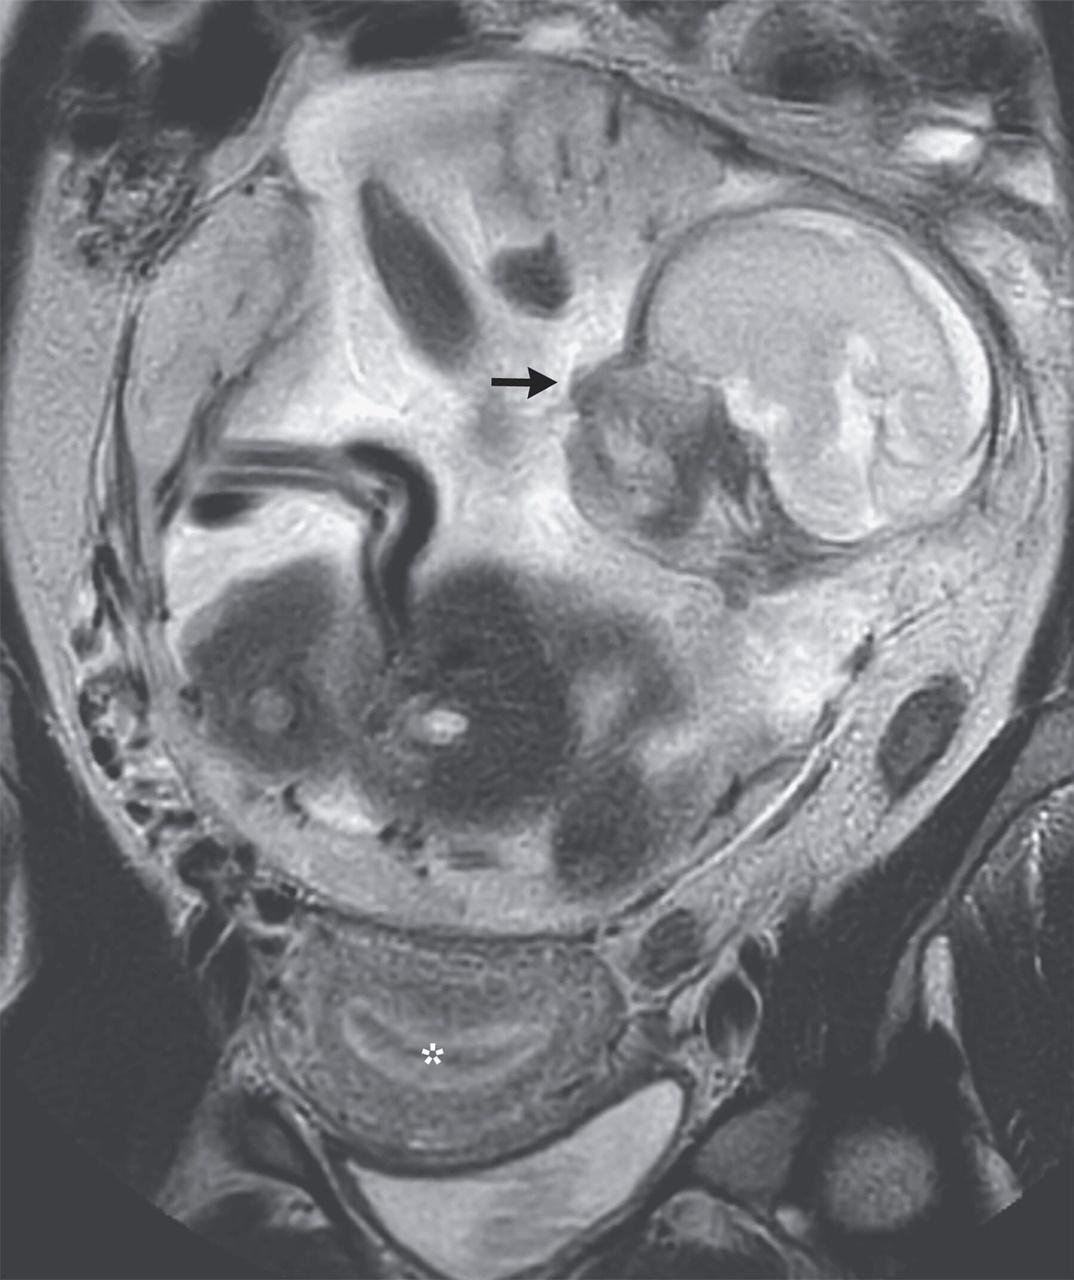

有關病例已發表於《新英格蘭醫學雜誌》(The New England Journal of Medicine),文章指出,該名法屬非洲印度洋島嶼Réunion婦女,在經過10天嚴重「胃痛」後前往急症室求醫,被發現在胃部與腸道之間子宮外孕,且胎兒奇跡般存活並發展到6個月大。

胎兒在胃部與腸道之間子宮外孕,且奇跡地存活並成長至6個月大。(網上圖片)

報告指出,雖然受精卵從輸卵管到子宮腔著床過程中,有可能因輸卵管破裂「逃離」子宮腔,但機率僅3萬分之1且「失去胚胎機率高達90%」,胚胎即使倖存也有「5分之1機率腦損傷或有先天缺陷」。院方為慎重起見,將女子轉送法國當地治療,醫院的團隊醫生判斷胎兒在8個月大手術,胎兒存活機率可達80到90%屬最高,建議女子等待5個星期以進行剖腹生產。

團隊先是成功把胎兒從腸胃之間取出,送往新生兒加護病房觀察,再於剖腹產2個星期後對女子進行腹腔胎盤清除手術。目前女子及嬰兒已出院,返回Réunion島上的家人團聚。